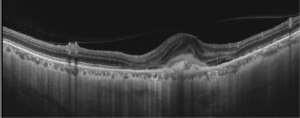

SD-OCT – Hyper-reflective lesions with fuzzy borders at the RPE, central ellipsoid, and external limiting membrane are seen on SD-OCT imaging. Generally, type 2 CNVM are seen in the pathological myopia cases. Subretinal hemorrhage, intraretinal fluid , subretinal fluid or RPE detachment may also be seen. Enhanced depth imaging (EDI) enables visualization of choroid layers as well which typically demonstrates atrophy in myopic eyes without CNVM and fibrosis or thickening in myopic eyes with CNVM present

SS-OCT – Swept source imaging is particularly useful for diagnosis and follow-up of myopic CNVM. Chorioretinal thinning along with subretinal membrane may be seen in SS-OCT in eyes with myopic CNVM (Fig 2, 3). Better delineation of choroid layers is also possible with SS-OCT.